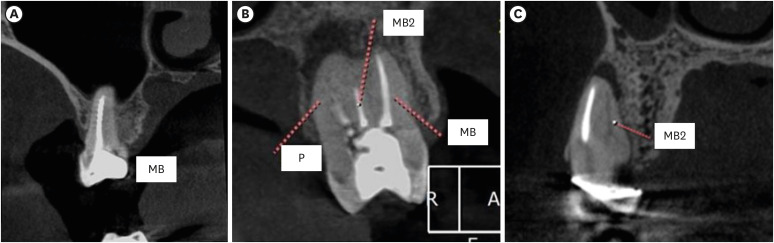

Figure 1

Representative images showing (A) satisfactory filling, (B) satisfactory filling (MB), unsatisfactory (MB2) and (C) Untreated (MB2).

MB, mesiobuccal; MB2, second mesiobuccal; P, palatal.